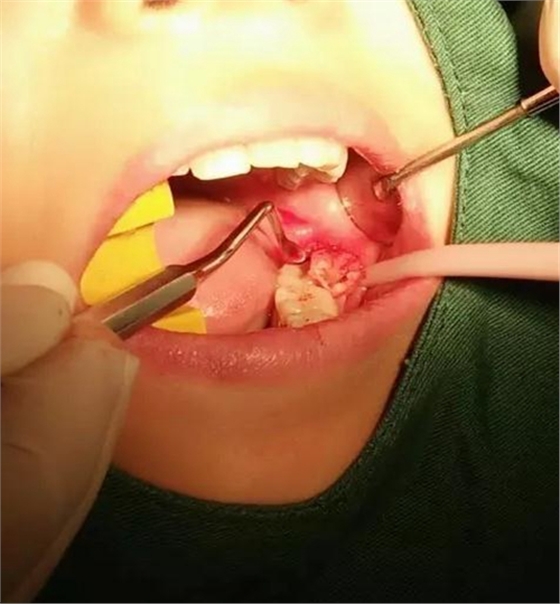

用到4號(hào)牙挺,避免敲擊拔牙根,稍有不慎,可能會(huì)出現(xiàn)牙根移位下頜神經(jīng)管。

挖匙取出

術(shù)中拍片發(fā)現(xiàn),還有剩余,繼續(xù)。。。。